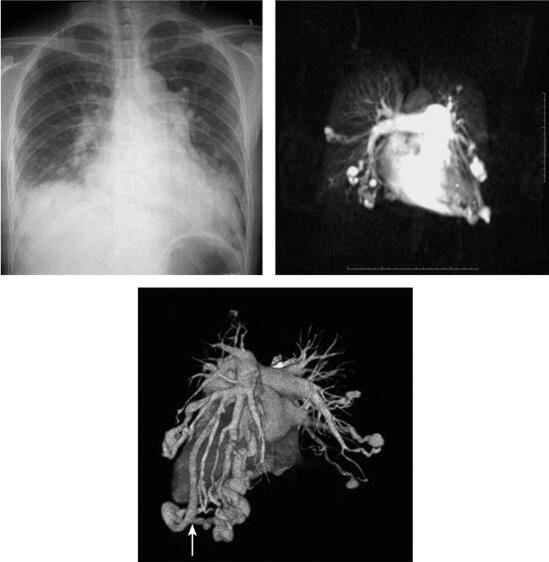

图1 肺动静脉瘘

X线平片表现:双肺纹理粗重,可见多个大小不等结节影,边界较清楚,密度均匀,心影增大,右侧膈面模糊,肋膈角消失。

肺动脉MRA表现:双肺内可见多个血管团,并可见供血动脉和粗大的引流静脉,部分瘤体有共同供血动脉或共同的引流静脉。

肺动脉CTA:所见与MRA相同。